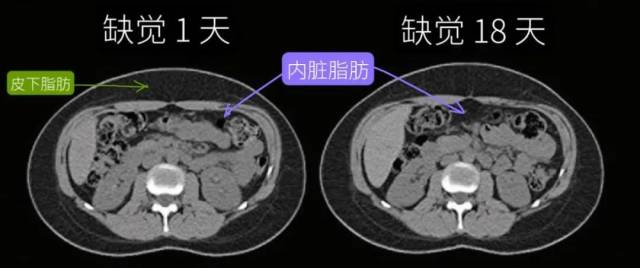

都是胖肚子,却有胖“皮下”和胖“内脏”的区别。

科学家在发现“缺觉会导致肚子长胖”后,又进一步分析了内脏脂肪的占比,得到了这样的结论:

睡饱睡足、不缺觉的人,即使不小心吃多、稍稍发胖一些,也主要是存在皮下,内脏脂肪面积没有出现明显增加。

反观缺觉的人,不仅更容易胖,内脏脂肪面积也足足增加了11%,就算是缺觉后立马补觉也无济于事。

缺觉时脂肪存储机制变化,更容易把脂肪转移到肚子内部,变成“内脏脂肪”,包围各大内脏器官,损伤心血管、影响身体代谢。